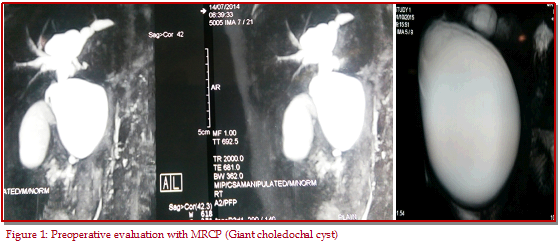

The aim of this study was to review our experience of total excision with Roux-en-Y hepatico-jejunostomy for the surgical management of type I and type IVa choledochal cysts in 30 children. Among them, 22 were in type I and 8 in type IVa choledochal cysts. All had complete excision and Roux-en-Y hepaticojejunostomy with no morality. Morbidity consisted of prolong drainage (n=2) and late onset cholangitis/pancreatitis (n=4). Choledochal cyst generally has an excellent prognosis with early complete excision and Roux-en-Y hepaticojejunostomy.